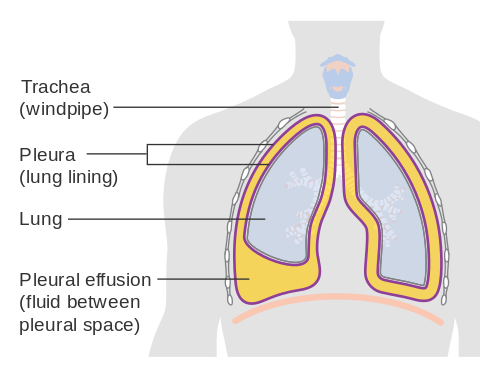

An effusion is an accumulation of extra fluid around the lungs and the membranes around the lungs. It is normal for there to be a small amount of fluid surrounding the membranes or pleura of the lungs, and it only becomes a problem when there is an excess quantity of fluid present.

A chest X-ray, CT scan or ultrasound can be used to detect and diagnose an effusion in the lungs. The effusion can be confused with an infiltrate but it is not actually within the lung tissue in the way that an infiltrate is. Analysis of the pleural fluid can help determine the cause of the effusion, which is important for determining the correct treatment options.

There are many reasons why an effusion may develop in the chest but the most common reason for an effusion to develop is congestive heart failure, resulting in an incorrect fluid balance in the lungs. Other causes include cirrhosis of the liver, open heart surgery complications, pulmonary embolism, tuberculosis, pneumonia, or kidney disease. An effusion often indicates an inflammatory response due to infection or compromised organs. An effusion is dangerous and leads to death in about 15% of afflicted patients.

A pulmonary infiltrate is when there is a substance in the lungs such as pus or blood that is not meant to be present. An effusion is when there is an excess of fluid that has accumulated between the pleural membranes surrounding the lungs.

Involves pleura

The pleura are not involved in a pulmonary infiltrate. The pleura of the lungs are involved in the case of an effusion.